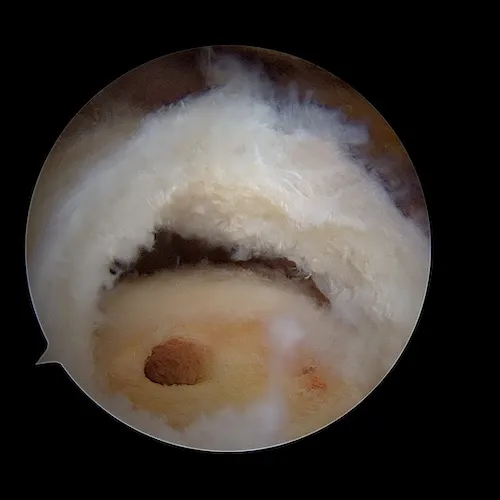

La réparation du (ou des) tendon(s) est réalisée sous arthroscopie grace à des ancres miniaturisées sur lesquelles sont fixés des fils très résistants qui permettent de réinsérer les tendons sur l'os pour permettre leur cicatrisation. Une acromioplastie et un geste sur le biceps (ténotomie ou ténodèse) sont le plus souvent associés.

Cette vidéo vous montre une procédure classique de réparation de la coiffe des rotateurs sous arthroscopie.Il s'agit d'images de synthèse. La technique utilisée est un double rang d'ancres. Les ancres médiales sont placées au ras du cartilage. Les ancres latérales qui servent à plaquer la coiffe sur le footprint sont placées à la face externe de l'Humérus. Les ancres sont montées sur des sutures non résorbables composées de fils et de bandelettes.

La rupture tendineuse est visualisée dans l'espace bursal sous la forme d'un "trou" dans le tendon. Les fibres tendineuses parthologiques sont réséquées afin de ne garder que du tendon sain. C'est ce tendon qui va être ensuite réinséré sur l'os.